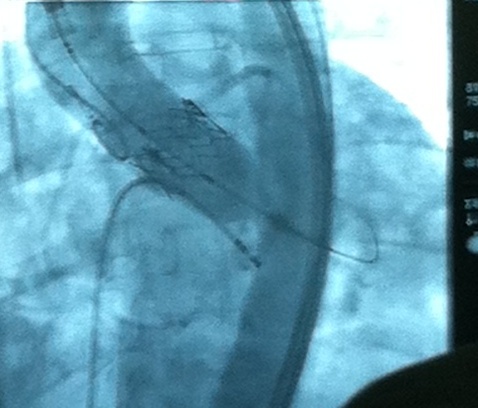

Сложная операция на сердце была проведена зарубежному представителю одной из крупнейших американских компаний в Казахстане. Операция была осуществлена в Центре кардиохирургии Национального медицинского холдинга в Астане. Накануне пациент,...

Новейшая технология сегодня внедрена в Национальном Центре Кардиохирургии Нацмедхолдинга: имплантирован...